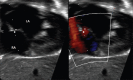

A patent foramen ovale (PFO) is a frequent incidental finding during echocardiography in otherwise healthy children. In most healthy children with a diagnosis of isolated incidental PFO, no further follow-up or intervention is necessary. In some children, PFO is associated with certain clinical syndromes such as cryptogenic stroke, decompression sickness, migraine, and platypnea-orthodeoxia syndrome. This review discusses PFO anatomy, diagnostic imaging, PFO-associated clinical situations, management options, and the role of PFO in certain congenital heart disease. This review also highlights the current deficiency of pediatric data guiding management of these uncommon but important PFO-associated conditions. Future multicenter randomized controlled studies are necessary to guide the management of these unique and challenging PFO-associated conditions.